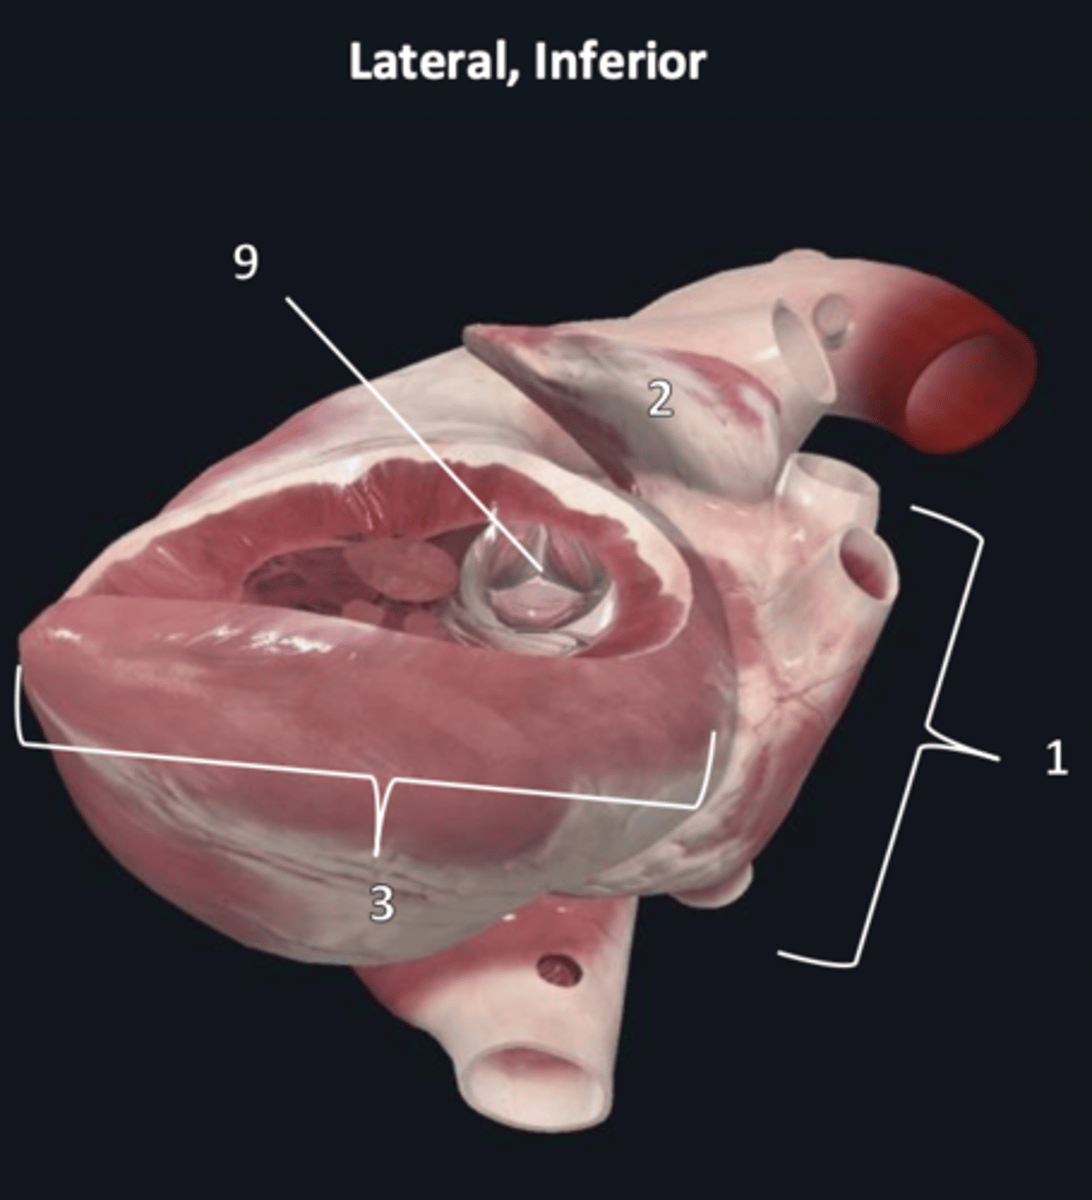

left atrium

1

left auricle

2

left ventricle

3

trabeculae carneae

4

inferior papillary muscle

5

superior papillary muscle

6

chordae tendineae

7

left atrioventricular valve

8 (opening)

aortic semilunar valve

9 (opening)